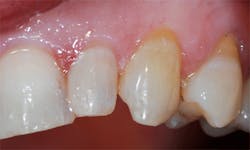

G-Premio Bond (GC America Inc.), a new universal eighth-generation bonding agent, was applied with a microbrush to all enamel and dentin surfaces and left undisturbed for 10 seconds. (figure 3). This was followed by application of a light air stream from the air/water syringe for 5 seconds to aid the evaporation of any remaining solvent in the adhesive, and then the bonding agent was light cured for 20 seconds. To ensure a thorough coating, a second coating of the adhesive was applied to the dentin areas of the prep and light cured.

A glossy surface on the dentin indicates that adhesive is fully coating the surface to be bonded. If any areas do not appear glossy, additional applications of G-Premio Bond can be applied. G-Premio Bond is compatible with total-etch, self-etch, and selective-etch techniques, providing excellent versatility for whichever technique the situation requires or the practitioner prefers.

Figure 3: G-Premio Bond was applied to the dentin and enamel margins and light cured for 20 seconds.